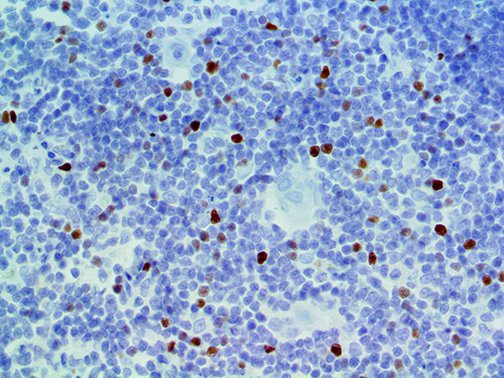

It is the ICU physician who is most likely to witness one of the deadliest manifestations of the abnormal immunological response, the cytokine storm syndrome (CSS). This response is also referred to by some as the cytokine release syndrome (CRS). CSS is characterized by continuous activation and expansion of macrophage and lymphocyte populations, which secrete large amounts of cytokines, causing the cytokine storm. This massive cytokine release is akin to hemophagocytic lymphohistiocytosis (HLH) disease, a syndrome characterized by initial unchecked and persistent activation of cytotoxic T lymphocytes and NK cells.

Clinical and laboratory manifestations of HLH include fever, enlarged liver and/or spleen, neurologic dysfunction, coagulopathy, liver dysfunction, cytopenias (i.e., low levels of erythrocytes, leukocytes, and/or platelets), hypertriglyceridemia, hyperferritinemia, hemophagocytosis, and eventually diminished NK cell activity as the immune system becomes progressively paralyzed. HLH can be familial (primary HLH) or secondary to another disease process (sHLH), such as rheumatic disease, in which it is referred to as macrophage activation syndrome (MAS, characterized by elevated ferritin).